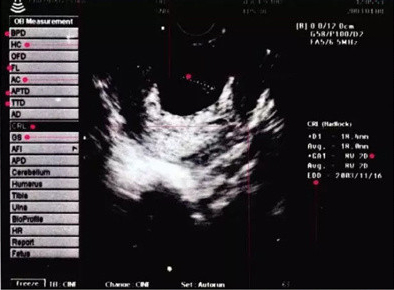

B超常用的专业语是什么意思?为了更好理解,我们看看下面这张B超图像。

左侧从上到下,记一下主要的几个缩写词。多了你们也记不住。

BPD:双顶径,指宝宝头部左右两侧之间最宽部位的长,用来判断胎龄,计算预产期。

HC:头围,确认宝宝成长发育的程度。

FL:股骨长,—般比BPD值小2-3厘米。用FL和BPD可以估计宝宝大小和体重。

AC:腹围。确认胎龄的基准。

AF:羊水指数.以孕妈的脐部为中心,分上、下、左、右4区域,将4个区域的羊水深度相加,就得到羊水指数,孕晚期羊水指数的正常值是8~18厘米,超过18厘米为羊水增多,少于8厘米为羊水减少。

GP:胎盘分级,一般为0.I.Ⅱ.Ⅲ级。

I级为胎盘成熟的早期阶段,回声均匀,一般孕30~32周胎盘为I级。

Ⅱ级表示眙盘接近成熟。

Ⅲ级表示眙盘已经成熟,胎盘内有很多钙化点。越接近足月,胎盘越成熟.回声越不均匀。